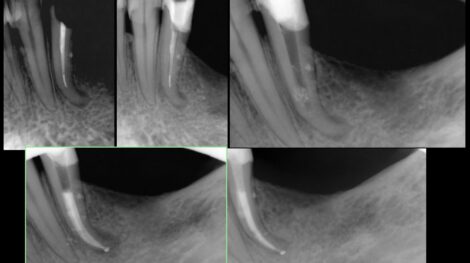

Leczeniem kanałowym zajmuję się od 14 lat i od samego początku była to dziedzina stomatologii paradoksalnie dla mnie najciekawsza. Po roku od ukończeniu studiów, aż do dnia dzisiejszego leczenie kanałowe stanowi 90% mojego czasu pracy.

Tak duża ilość przypadków od najprostszych do ekstremalnie skomplikowanych pozwoliła mi przeprowadzać zabiegi w sposób przewidywalny, sprawny i z minimalnym ryzykiem powikłań.